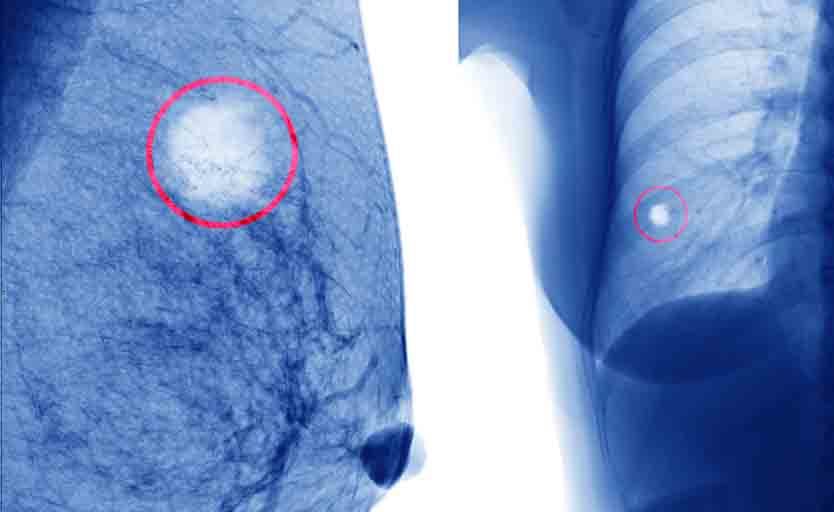

• mammografia, una radiografia del seno può aiutare a distinguere tra masse benigne e maligne;

Cancro al seno: quali sono i sintomi?

La maggior parte dei noduli al seno è causata da condizioni non gravi. La comparsa di grumi, anche indolore, è comunque il sintomo più comune di cancro alla mammella. Vi sono altri segnali che possono essere legati a cancro al seno e che è bene non trascurare: